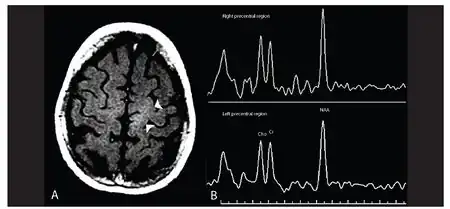

Primary lateral sclerosis -a)Image shows abnormal hyperintensity in left subcorticol precentral region b) image shows reduced NAA peak and NAA:Cr ratio in the left brain hemisphere | |